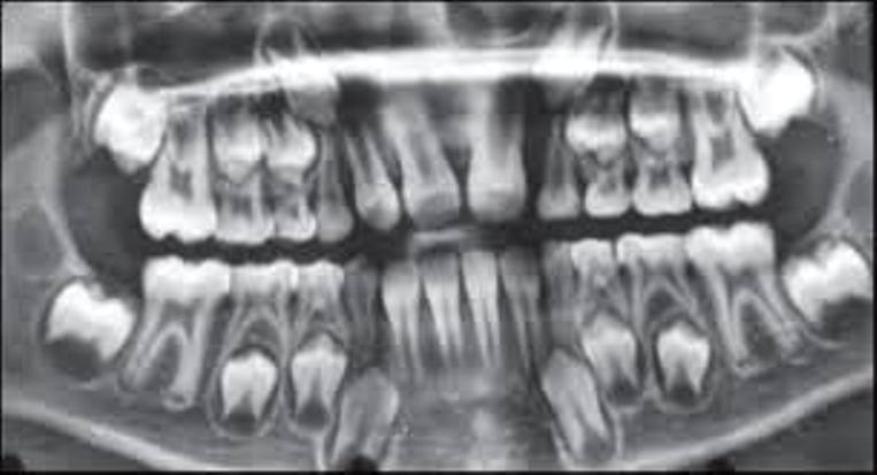

BELOW ARE X-RAYS OF ACTUAL PATIENTS

Hyperdontia is the condition of having supernumerary teeth, or teeth that appear in addition to the regular number of teeth. They can appear in any area of the dental arch and can affect any dental organ.

There is evidence of hereditary factors along with some evidence of environmental factors leading to this condition. While a single excess tooth is relatively common, multiple hyperdontia is rare in people with no other associated diseases or syndromes. Many supernumerary teeth never erupt, but they may delay eruption of nearby teeth or cause other dental or orthodontic problems. Molar-type extra teeth are the rarest form. Dental x-rays are often used to diagnose hyperdontia.

It is suggested that supernumerary teeth develop from a third tooth bud arising from the dental lamina near the regular tooth bud or possibly from splitting the regular tooth bud itself. Supernumerary teeth in deciduous (baby) teeth are less common than in permanent teeth.